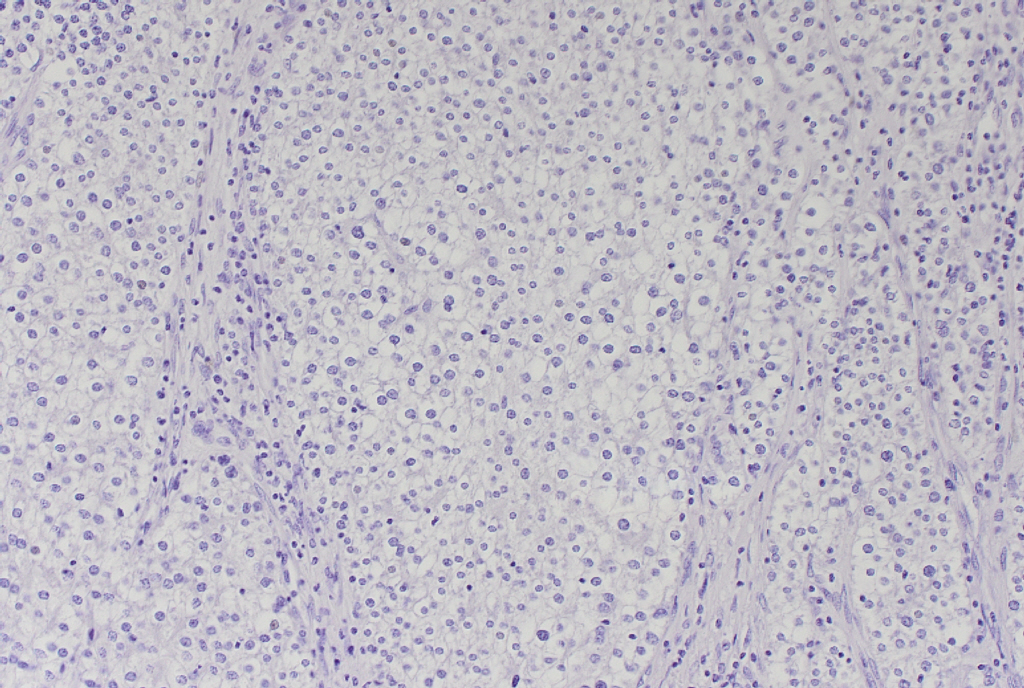

手術後の組織診の免疫染色にてカルシトニン陰性、クロモグラニンAとシナプトフィジン陽性の結果より、副甲状腺癌と診断された症例であった。

HE カルシトニン クロモグラニン シナプトフィジン